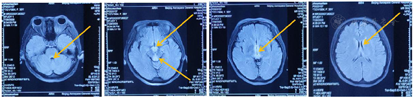

吞咽器官功能评估:面部肌肉力量弱,缩唇及撅嘴幅度小;吞咽反射功能评估:呕吐反射减弱,咳嗽反射减弱,咳嗽力量弱,吞咽反射延迟;喉功能评估:喉上抬幅度小,咳嗽声音小;感觉评估:右侧面部针刺觉稍减弱;右侧口腔内温度觉稍减弱。VFSS吞咽造影:食物进入气道,进入声带以下,无用力清除表现。患者存在构音障碍及吞咽障碍(图2、图3)。

病生理方面,本患者存在认知记忆障碍、平衡协调障碍和吞咽构音障碍。此外还有眼震和眼肌麻痹。记忆障碍可能与间脑结构(丘脑、下丘脑和乳头体)受损有关,与内侧颞叶损伤引起的记忆障碍类似。眼部异常症状与中脑和脑桥的外展神经核和眼球运动中心受损相关,躯干四肢的共济失调及吞咽构音相关肌肉的运动失调可能与小脑蚓部受损有关[10]。